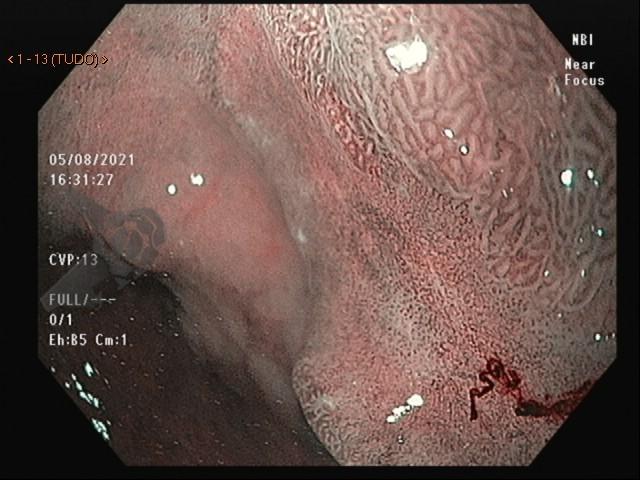

3. EDOF (Extended Depth of Field)

A incorporação do EDOF, ou campo de visão estendida, proporcionou uma melhora significativa na qualidade de imagem. Com o sistema anterior, o Near Focus produzia uma imagem ampliada, porém para atingirmos uma boa resolução, tínhamos que nos aproximar muito do foco de interesse e a imagem ao redor ficava desfocada. Para melhorar nesse aspecto, dois refletores (espelhos) foram colocados na ponta do aparelho, permitindo ver uma área de interesse de perto, porém mantendo a nitidez da área ao redor.